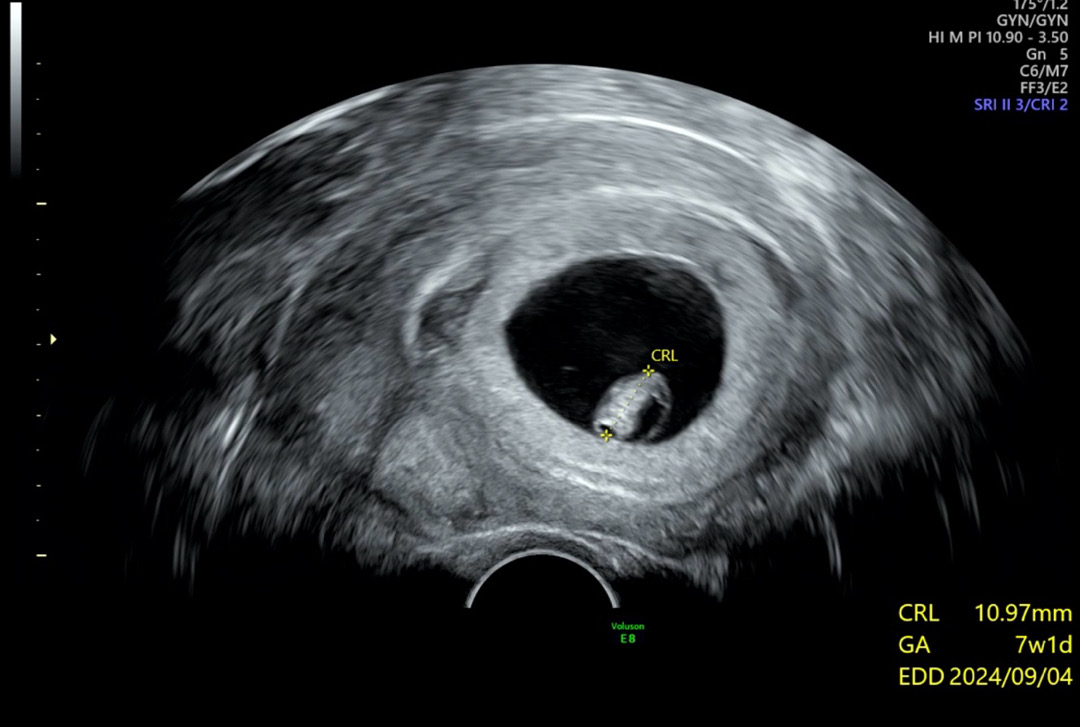

예정일 9/9 7주 1일 1.02cm 보고왔어요:-)💖

7주 1일차 아기 크기 10.97mm 괜찮은가요?

안녕하세요 😊 예정일은 9월 5일이고 현재 오늘 기준으로 8주 0일 됐는데 일주일 전에 보고 온 초음파예요! 7주 1일 10.97mm 였어요 의사선생님이 딱히 별말씀 안해주셔서 오늘에서야 다시 보니 아기 크기가 요맘때 어느정도인지 궁금하네요! 다들 아기 크기 어떻게 보셨나요?!?!

7주2일에 1.1cm 이었어요 ㅎㅎ

예정일 9/5 7주5일 1.6이요~! 일주일 전이니까 지금 8주면 더 많이 컸을거에요 ㅎㅎ

예정일 9월5일 오늘 진료 7주5일 1.36cm 이틀정도 늦다고하셨는데 오늘은 하루 따라잡았다고 하시네요ㅎㅎ 걱정하지마셔요!